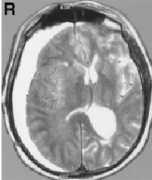

右側(cè)三叉神經(jīng)根底部的動靜脈瘤樣結(jié)構(gòu)(AVM)破裂而導(dǎo)致蛛網(wǎng)膜下腔出血。與以前的病例相比,他的病史中沒有三叉神經(jīng)痛或感覺喪失的證據(jù)。右椎動脈造影顯示小腦上動脈雙倍供血于...